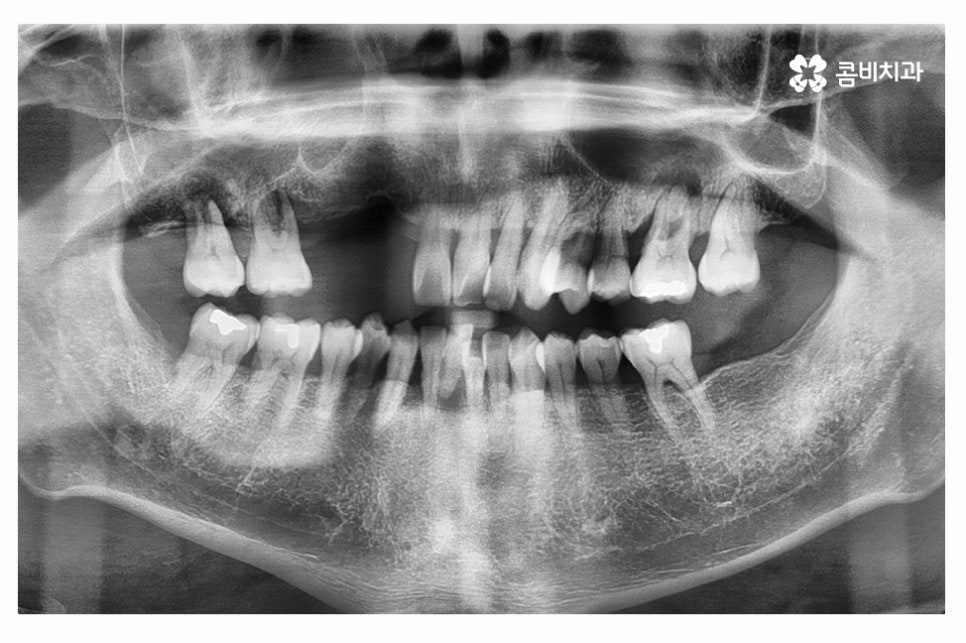

중년 이후에는 치아 상실의 원인이 치주질환으로 인한 경우가

많기 때문에 위 엑스레이 사진에서 보시는 것처럼

치아 자체는 멀쩡해 보이지만 잇몸 상태가 악화되어서

치아를 발치하고 임플란트 수술을 하는 경우가 많다고 볼 수 있어요.